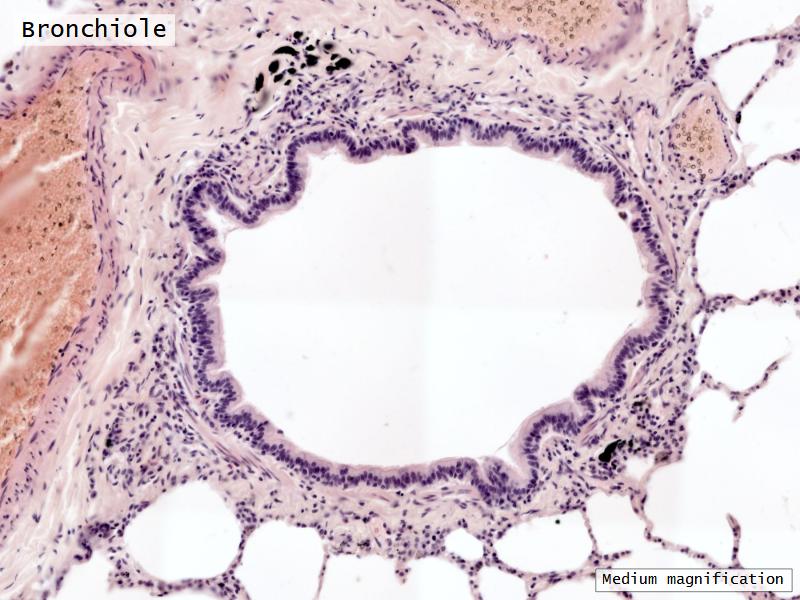

- Bronchioles

- Smooth muscle REPLACE cartilage

- Ciliated columnar > Ciliated cuboidal

- NO glands - goblet cells -> secretory cells

- Terminal bronchioles

- Smooth muscle

- Ciliated cuboidal epithelium

- Secretory cells